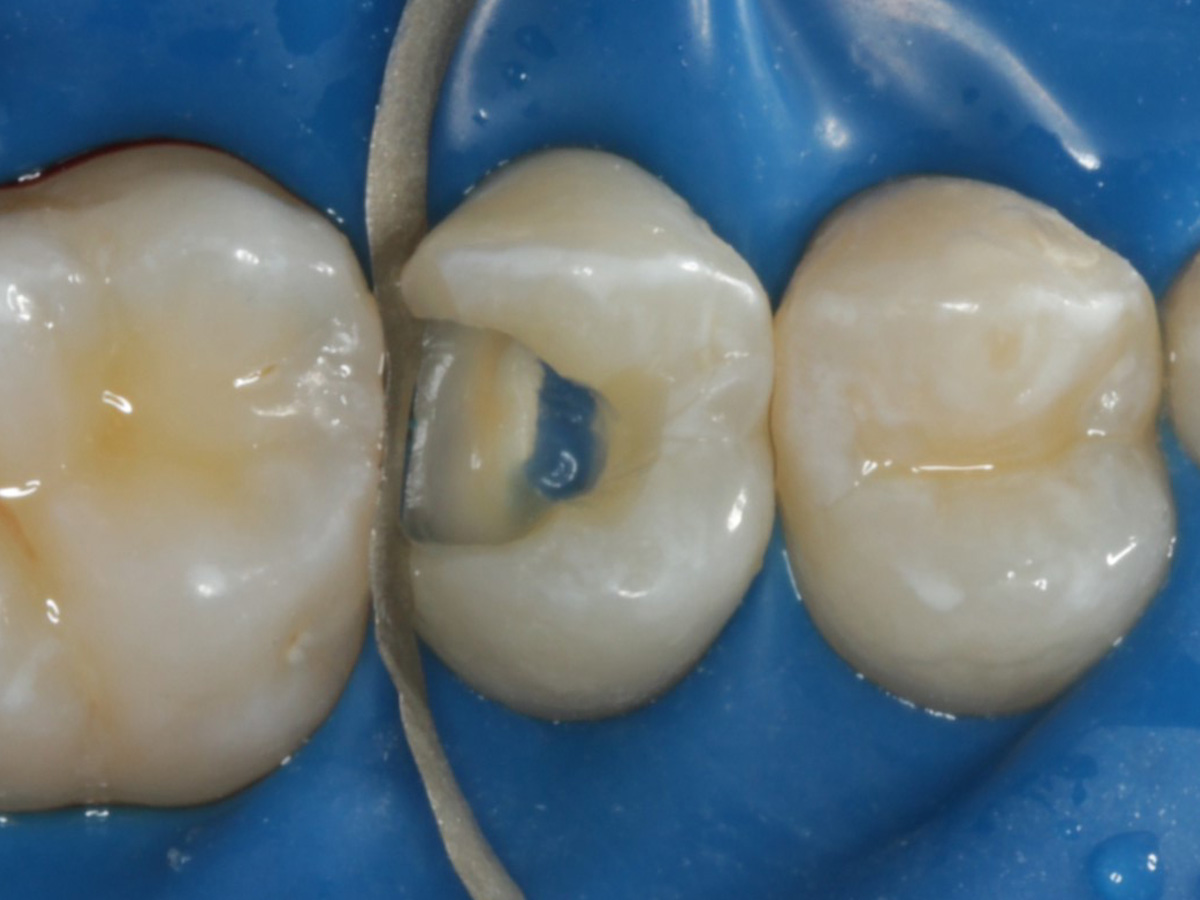

Abbildung 2

Intakte Kaufläche

Abbildung 5

Height Indicator vor Auswahl der passenden Evolve Matrize nach Defektdarstellung, Kariesexcavation, Vitalexstirpation